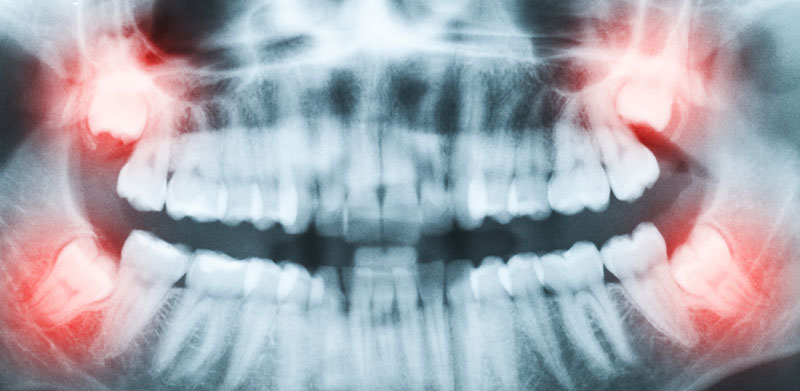

植牙之前,會先進行全口檢查與評估,透過3D電腦斷層掃瞄、X光輔助,進行精細的口內資料蒐集,依照口腔術聚及個人需求規劃出每個人專屬的植牙治療計畫。